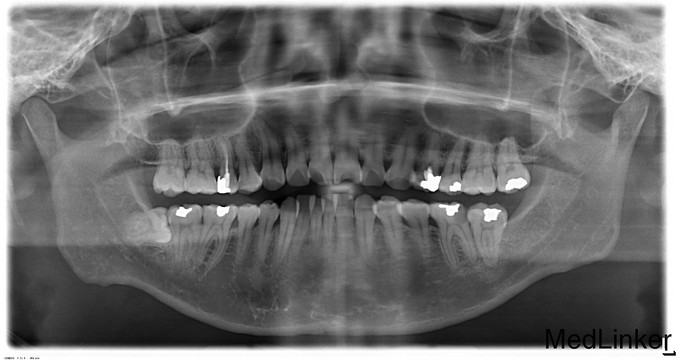

患者诉右下智牙反复肿痛史,曾咨询检查过,怕痛为处理,左下后牙长期冷热疼痛史

48处牙龈充血,可见部分牙冠,叩痛(-)无松动,36远中邻颌面深大龋洞,探痛明显,冷测轻微不适,热测疼痛,叩痛(-)

48阻生呀 36 慢性牙髓炎